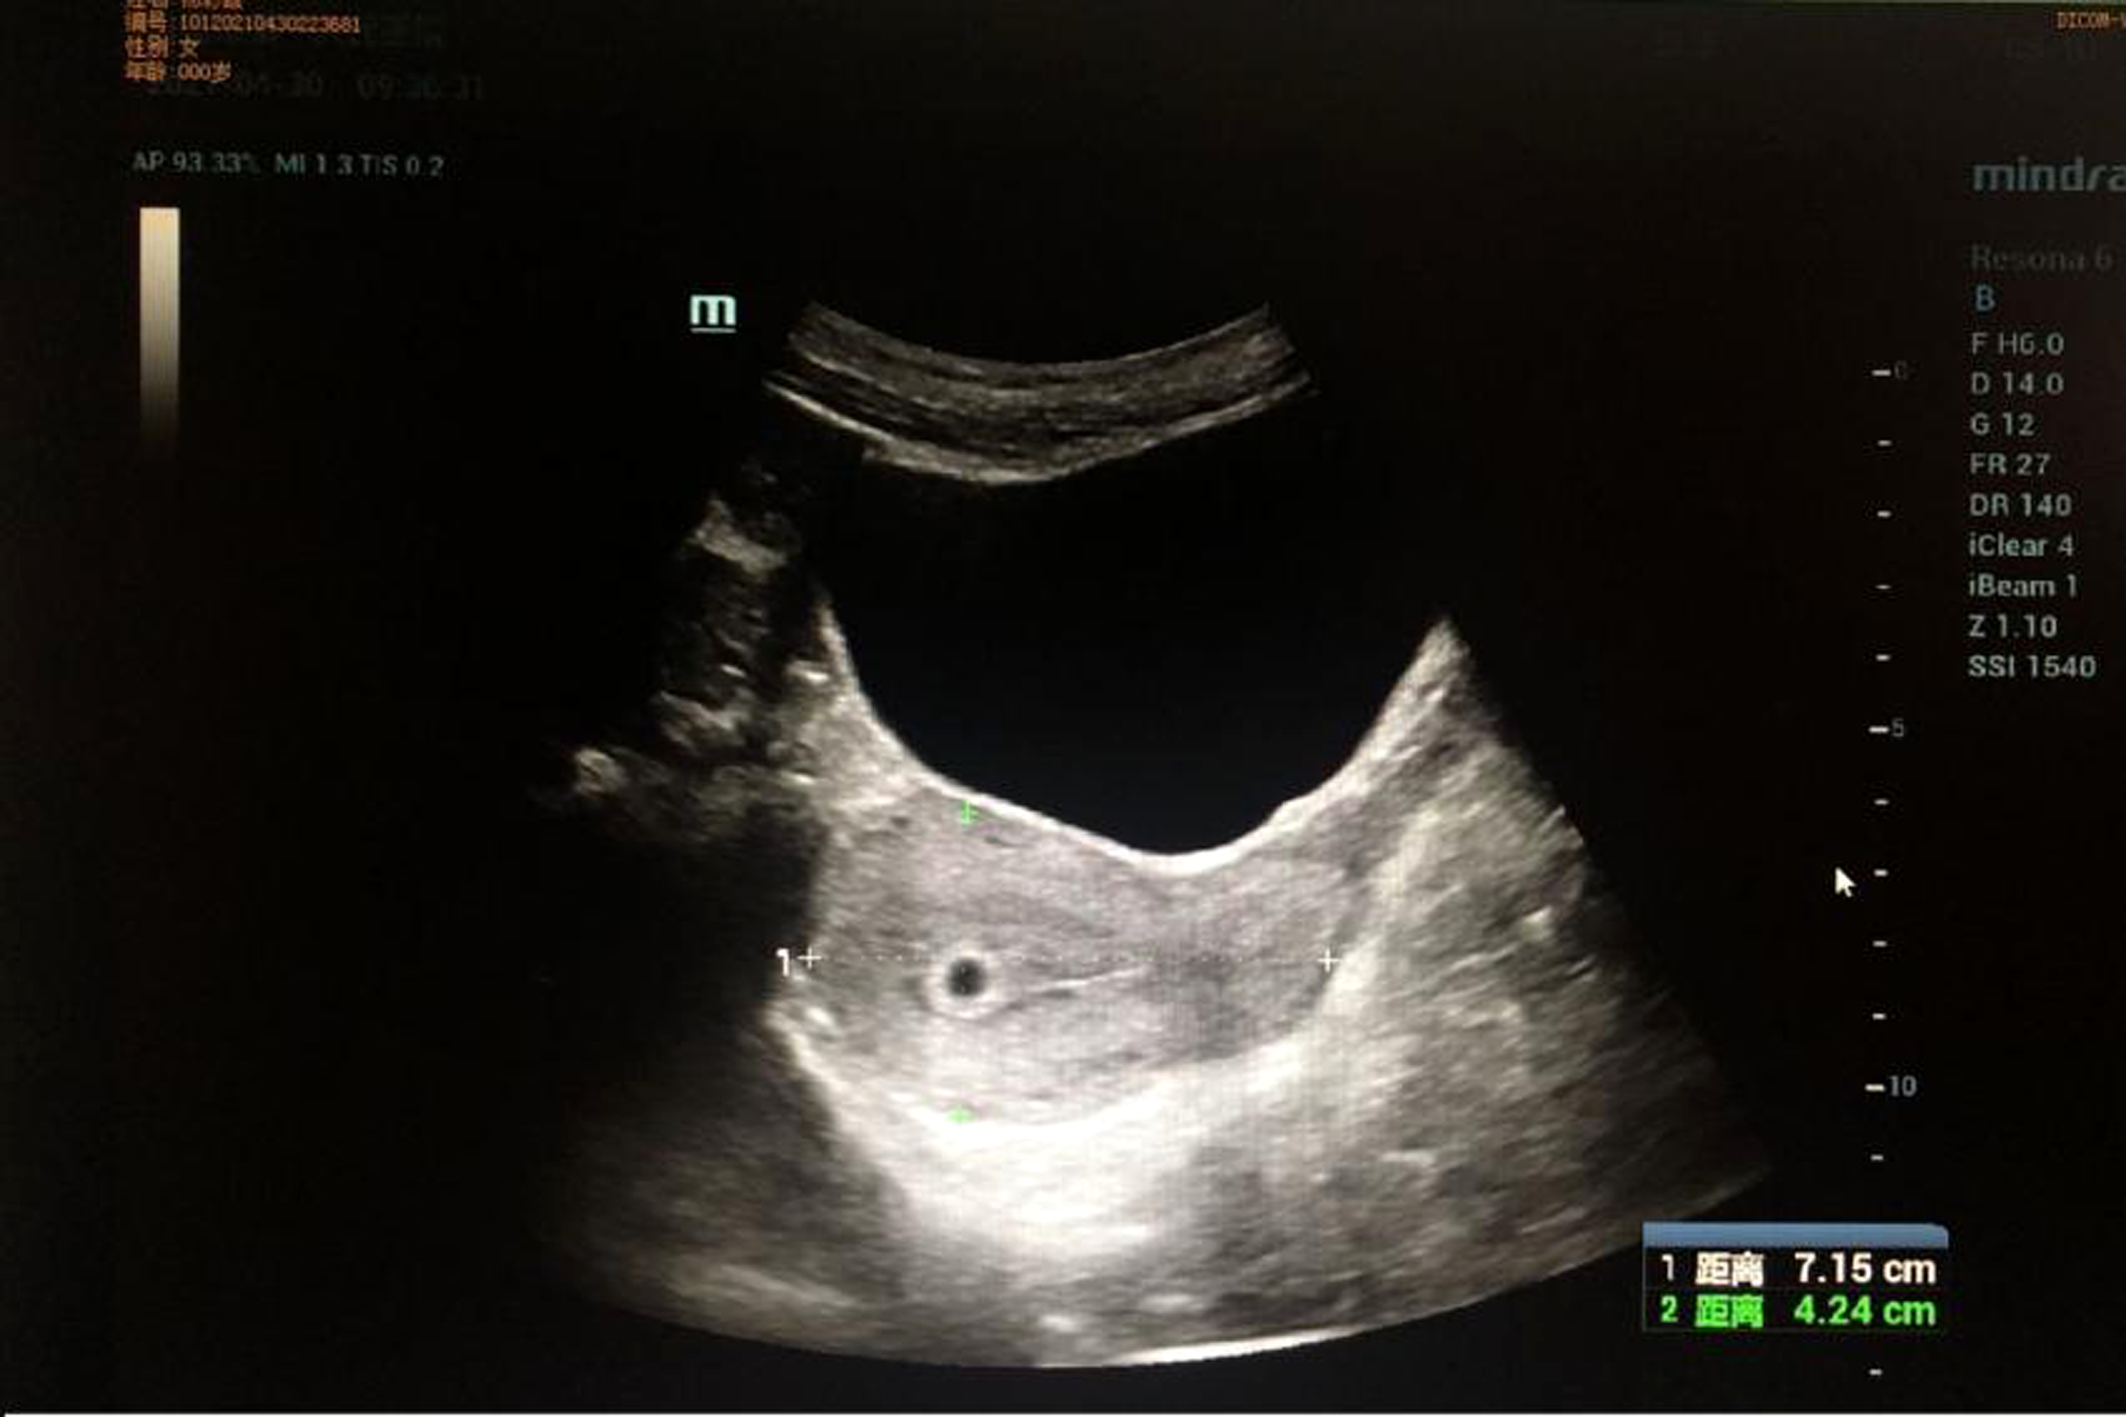

The patient was discharged on February 3, 2021. Adjuvant chemotherapy was strongly recommended, but she chose traditional Chinese medicine (TCM) instead. She came to our department as an outpatient for a checkup in April 2021. Enhanced CT scanning of her whole abdomen revealed multiple niduses in the liver, the largest being 2.6 cm, which indicated metastatic lesions (Figure 4). At the same time, she showed signs of cessation of menstruation, but an intrauterine gestational sac was found by color ultrasonography examination at the last follow-up on April 23 (Figure 5). This pregnancy was later spontaneously aborted.

Ultrasound imaging: The gestational sac in the uterus was detected by ultrasound examination.